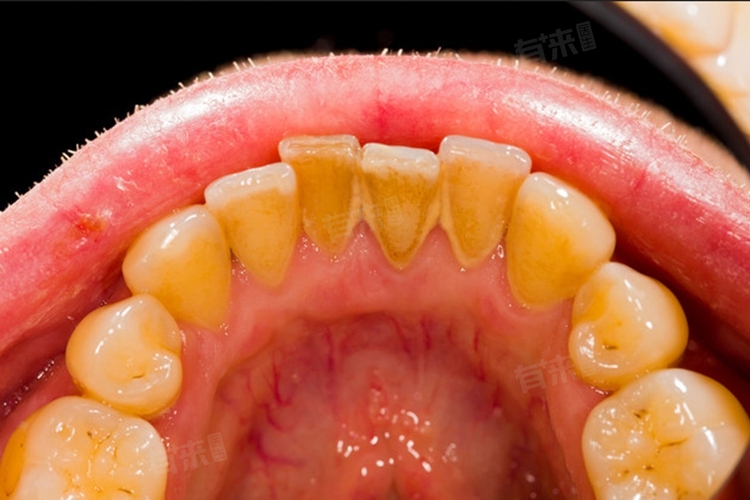

4、定期洗牙:洗牙是专业去除牙斑和牙结石的方法,通过超声波洗牙设备,利用高频振动去除牙齿表面和牙龈下的牙斑、牙结石。建议每年或每半年洗牙一次,可有效清除刷牙等日常清洁无法去除的顽固牙斑,维护牙龈健康,预防牙周疾病。洗牙后,牙齿更易清洁,能减少牙斑再次堆积速度。